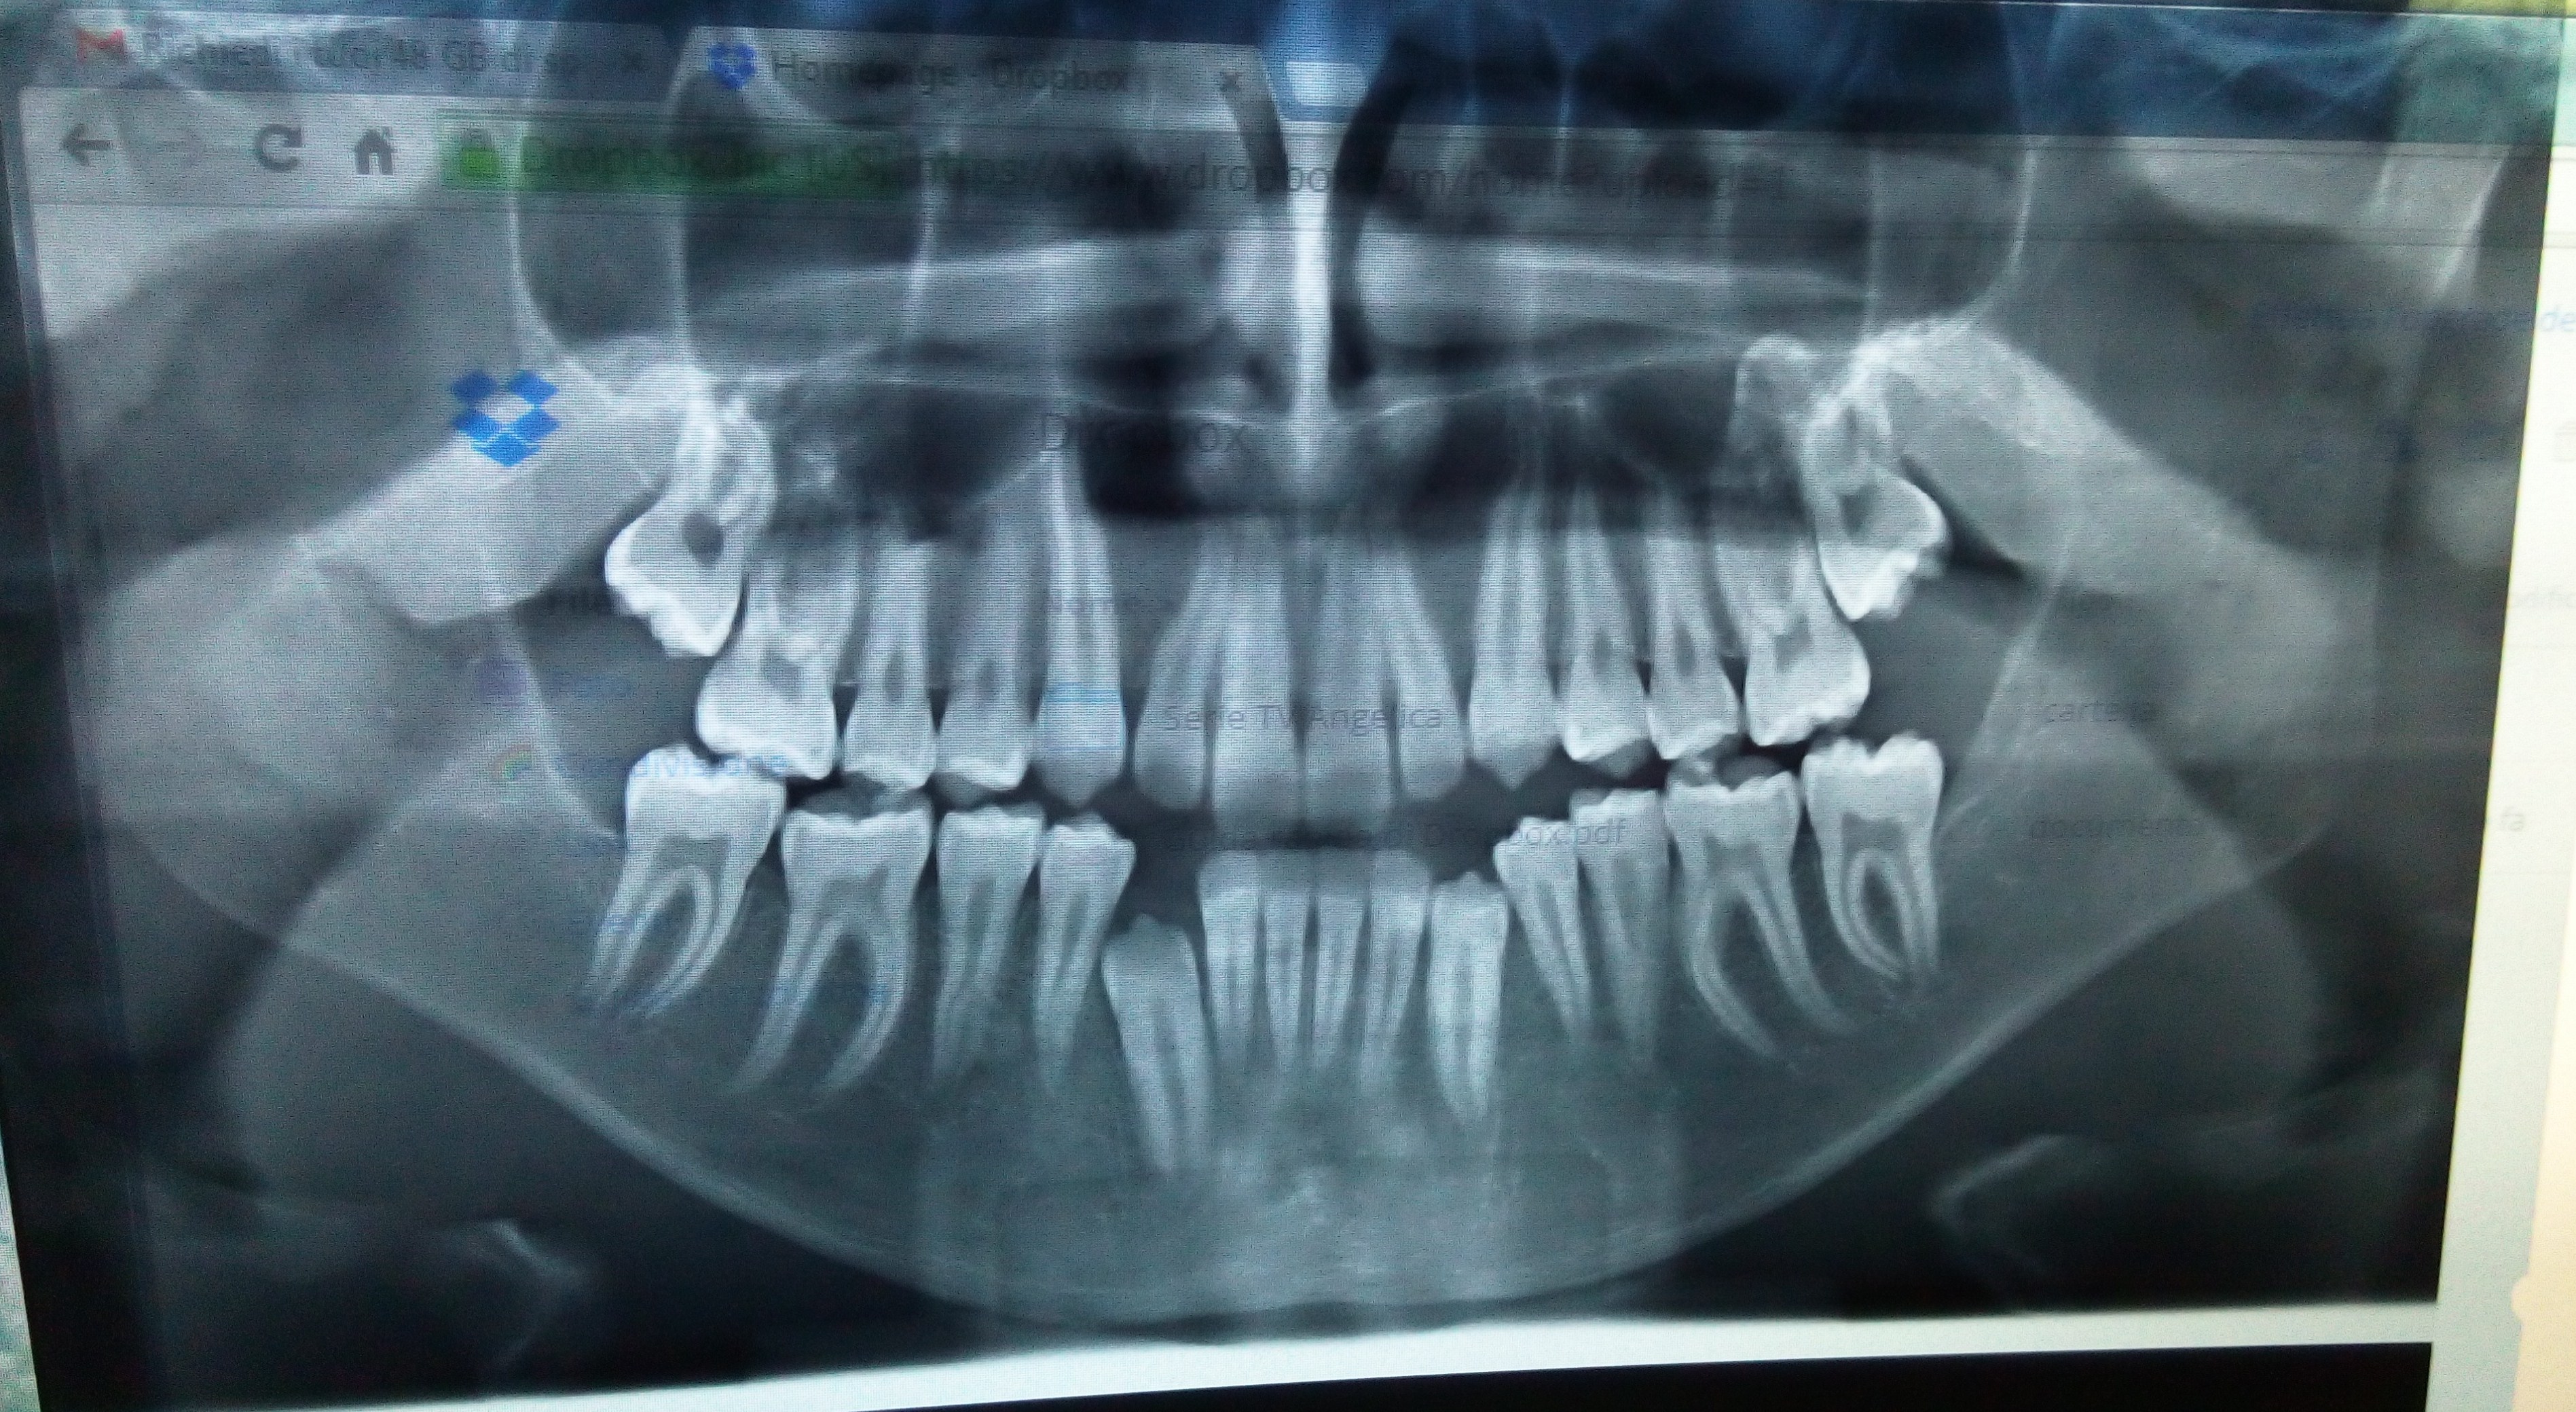

Ho tutti e 4 i denti del giudizio da estrarre

Buongiorno vi espongo dei piccoli dettagli tecnici per capire un po' la mia situazione per poi porvi il mio quesito. Ho tutti e 4 i denti del giudizio da estrarre, sono una seconda classe e ho un agenesia dell'incisivo laterale sx e conoide sulla destra. In questo momento sul lato sinistro dove non c'è posto per un impianto mi è

Mio figlio di quasi 14 anni è in cura da 3 anni e mezzo circa da un ortodontista

Buongiorno! Mio figlio di quasi 14 anni è in cura da 3 anni e mezzo circa da un ortodontista per problemi di affollamento e stortura denti ed ora morso aperto (quando è entrato non lo aveva od era poco evidente). Entrato con ortopanoramica e telecranio il dentista con fare allarmato mi dice che è curabile in due anni con